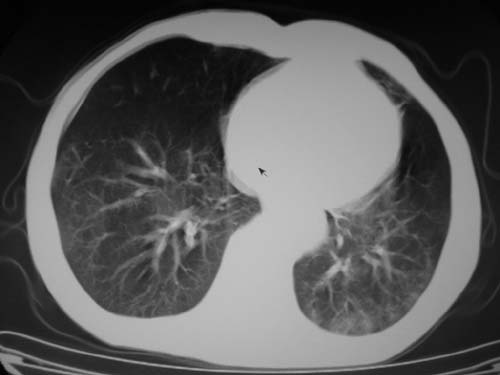

标题: CT19736:男,76岁,咳嗽,胸痛 [打印本页]

标题: CT19736:男,76岁,咳嗽,胸痛

支持左上肺周围型肺癌性并空洞形成伴胸椎转移。

左上沟癌空洞形成并胸椎转移。

考虑癌性空洞并胸椎转移。

空洞内壁有多发结节,支持癌性空洞。

支持左上肺周围型肺癌并空洞形成伴胸椎转移。z左下肺炎